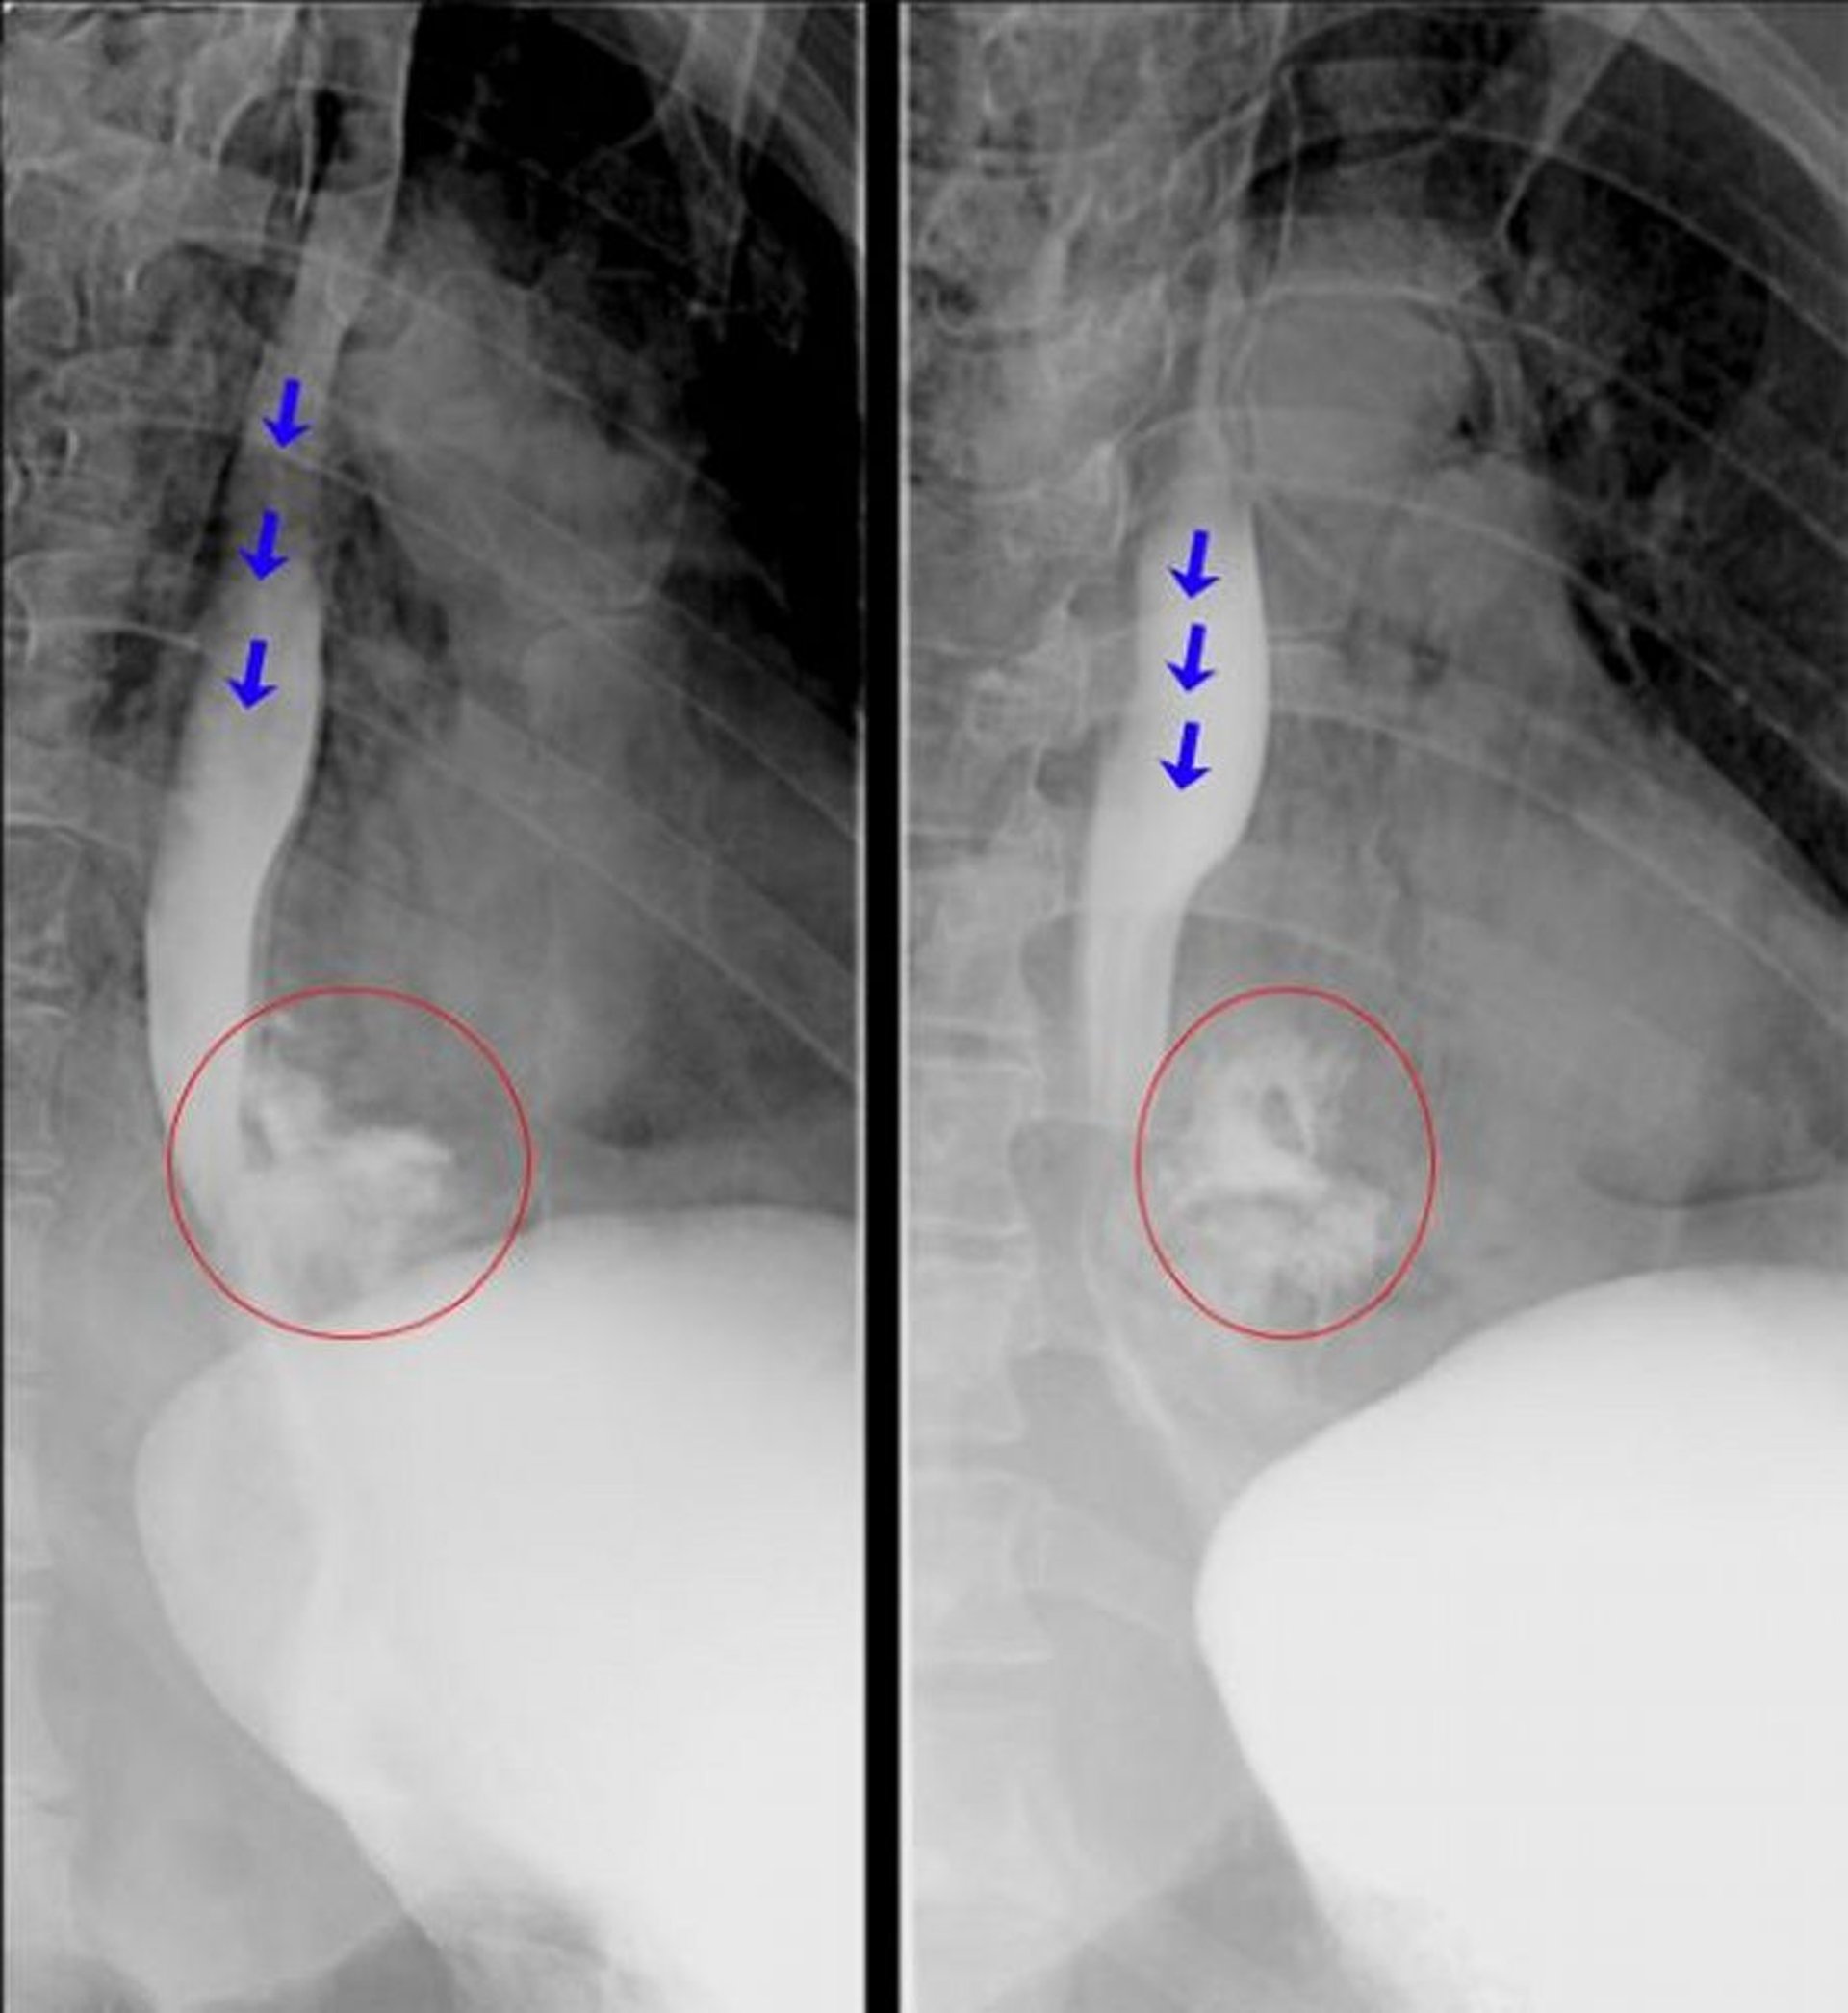

Эзофагография с водорастворимым контрастом

Эти рентгеноскопические эзофагограммы показывают явную экстравазацию контрастного вещества из дистального отдела пищевода, что согласуется с диагнозом перфорации пищевода. Синие стрелки указывают на контрастное вещество в просвете пищевода. Красными кружками выделено контрастное вещество, вышедшее из пищевода.